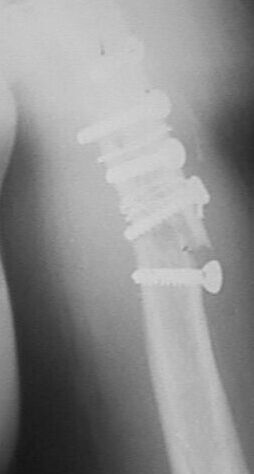

фас+профилькосые

Больная оперирована в апреле 2002 г, иммобилизация в течение 3 месяцев.После операции были явления неврита лучевого нерва, которые в последующем исчезли. Во время проведения ЛФК отмечает появление болей. В настоящий момент имеется патологическая подвижность в месте перелома, деформация плеча. У нас мнения разделились в тактике дальнейшего ведения.

1. провести репозицию закрытую и продолжить иммобилизацию гипсовой повязкой.мотивируя опасностью повторного повреждения лучевого нерва при повторной операции.2. провести открытую репозицию, удаление фиксаторов, остеосинтез накостный костной пластикой.3. репозиция, фиксация отломков аппаратом внешней фиксации спицестержневого типа.